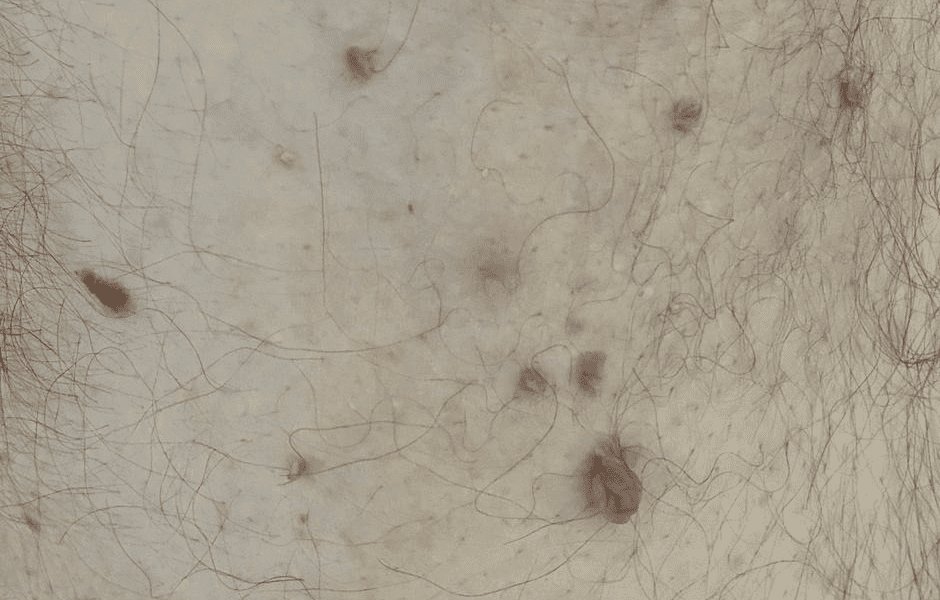

Às vezes confundido com verrugas ou pintas, ele apenas traz desconforto estético, pois não há risco de evoluir para câncer. Pode aparecer apenas um ou muitos e em homens e mulheres de maneira igual.

Em geral, o acrocórdon tem o mesmo tom da pele — ou um pouco mais escuro—, não apresenta sintomas e varia entre 2 mm e 10 mm, porém, a tendência é de que cresça e não regrida (a menos que seja removido, o acrocórdon dura a vida toda). O diagnóstico é clínico, feito por um dermatologista, não sendo necessário nenhum exame complementar.

Ao tocar no acrocórdon, ele se mexe facilmente para frente e para trás, sem dor, entretanto pode ficar irritado com o atrito. Caso ele fique retorcido, um coágulo sanguíneo pode se formar em seu interior, deixando-o dolorido.